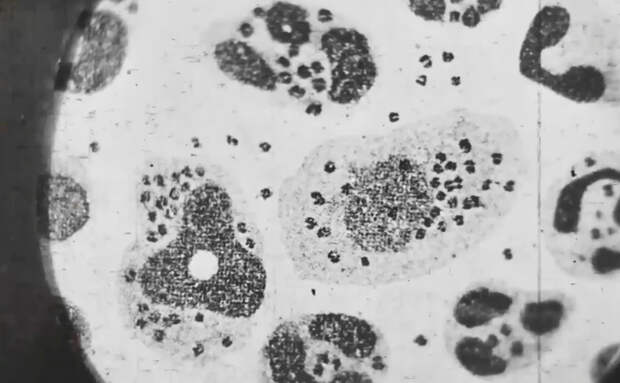

Правильный диагнозВрачи не могли понять, чем болен знаменитый плакатист. Правильный диагноз ему так и не смогли поставить. Во всяком случае пока он был жив. В официальных документах указано, что пациент умер от токсической формы чумы. Вскрытием руководил академик Николай Краевский. Он позволил присутствовать при этом своему приятелю из Ленинграда, 75-летнему патологоанатому.

Да это, батенька, variola vera – черная оспа,

- сказал гость столицы, лишь мельком взглянув на распластанное на столе тело.

Второй причиной стала убеждённость советских медиков о полной победе над оспой. Регулярная вакцинация детей и взрослых позволяла им оставаться здоровыми, несмотря на единичные случаи заражения на окраинах страны. Тему оспы проходили в медвузах, но врачей, которые в своей практике видели бы больных с этим диагнозом, было не так уж много. Пожилой патологоанатом потому и смог быстро и точно установить причину смерти, потому что не раз сталкивался с пациентами, заразившимися оспой.